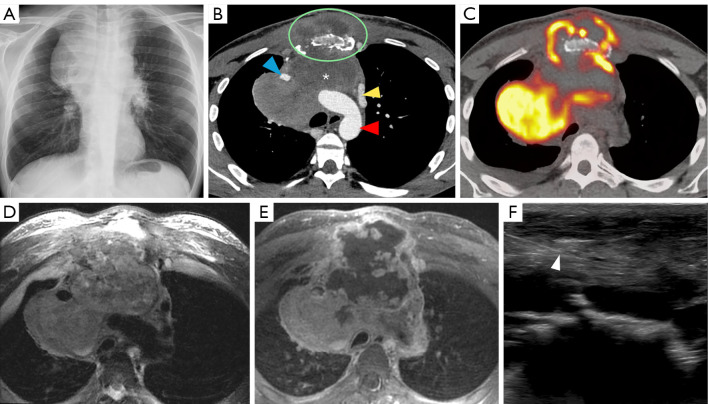

Abstract Image